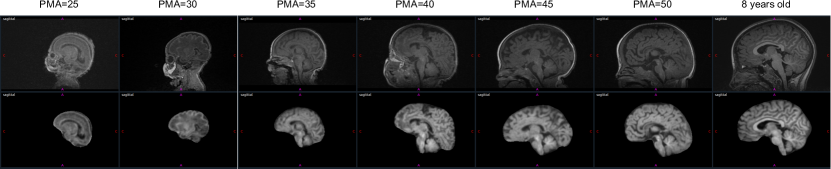

Across different datasets (Table 5, our method consistently achieved higher DICE (F1) scores, lower MSD values, and higher recall and accuracy rates compared to BET, NPP, and SynthStrip, highlighting its robustness and effectiveness in diverse segmentation tasks. Figure 3 illustrates a 3D MRI image along with the corresponding reconstruction and segmentation outcomes obtained using the proposed MGA-Net.

Refer to caption

Figure 3: From left to right: MRI image from an eight-year-old patient at HUPM, the reconstructed image using MGA-Net, and the brain boundary.

Figure 9 presents the three views of an eight-year-old preterm-born patient with reconstruction using NPP, U-Net, and the proposed method. As can be seen, the proposed method can successfully reconstruct the image even though there is an anomaly in the image, whereas NPP and U-Net have some problems in reconstructing the entire image (red circle in Figure 9.

The dataset obtained from Hospital Universitario Puerta del Mar (HUPM) originates from clinical settings, involving preterm neonates who may present with neurological abnormalities, such as abnormal tissue structures or atypical brain morphology (Figure 8). Some of these patients have been incorporated into the training dataset, while others are allocated to the test dataset to evaluate the model’s generalizability and robustness. Despite the inherent challenges associated with these variations, the results demonstrate that the performance of the proposed method on the test dataset is superior to that of conventional methods. This indicates that the proposed method can be effectively accommodated and adjusted for clinical abnormalities in its analyses. We attribute this robustness to the network architecture, which enhances its ability to generalize across uncommon and variant anatomical features.

Figure 9: Coronal, sagital and axial views (from left to right) of an eight-year-old preterm-born patient. The top image is the initial image.